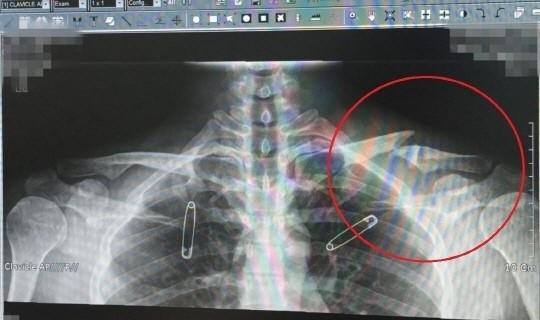

据韩媒,涉嫌吸毒的演员刘亚仁近日又被起诉兵役特惠,韩国兵务厅兵役调查科15日受理了以“请调查刘亚仁的兵役判定是否按照适当的程序进行”为宗旨的信访。刘亚仁在2013年拍摄电影时右肩肌肉破裂,并在2015年被确诊为骨肿瘤,无法服兵役。

当时刘亚仁表示:“2015年12月,2016年5月,经过法庭收到了征兵检查结果7级”,“将骨折受伤是治愈,不能正确地预测,但骨肿瘤的非正常发育不追加进行充分履行兵役义务的可能。”

之后刘亚仁在2017年6月得到了兵务厅最终免除兵役的判定。经纪公司UAA表示:“将把演员的健康问题放在首位,积极支援治疗,将进行慎重的观察和细心的管理。”